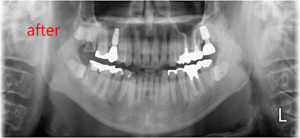

治療後の全体の写真とレントゲン写真がこちらです。

こちらがインプラント治療を終えた歯です。

その後、左上の一番奥の歯も同様の流れでインプラント治療を行いました。